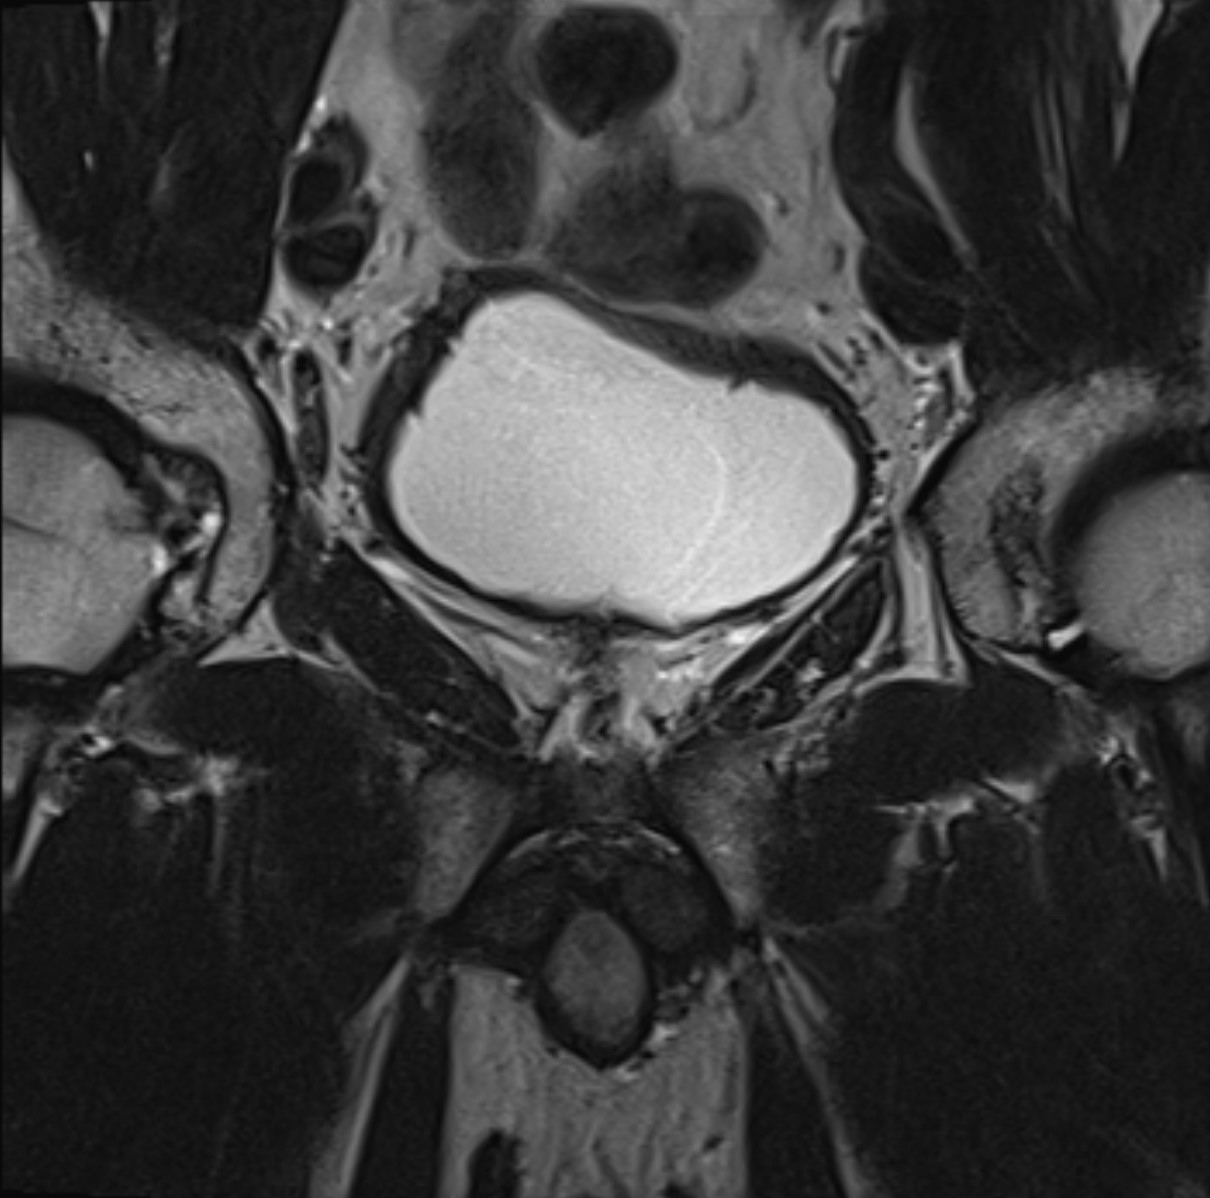

Förhöjt PSA-värde, behov av att kissa ofta, svag urinstråle eller blod i urinen kan vara tecken på förändringar i prostatakörteln. MR prostata är en avancerad och icke-invasiv undersökning som ger detaljerade bilder av prostatans anatomi och vävnadsstruktur – ett viktigt verktyg vid tidig upptäckt av prostatacancer eller andra sjukliga förändringar.

Magnetkameraundersökning är överlägsen både ultraljud och klinisk undersökning när det gäller att identifiera misstänkta områden i prostatan. MR används också inför eventuell vävnadsprovtagning (biopsi), för att minska risken för att missa tumörer, eller för att följa upp tidigare fynd. Undersökningen är helt smärtfri och fri från strålning.

MR Prostata används för att hitta tidiga tecken på prostatacancer och andra förändringar i och runt prostatakörteln. Undersökningen hjälper till att skilja mellan godartade och elakartade tumörer, vilket minskar behovet av onödiga vävnadsprov (biopsier). Man kan även se förstoring av prostatakörteln (BPH), tecken på inflammation (prostatit) och förändringar i sädesblåsorna. MR Prostata ger också information om lymfkörtlar i nedre bäckenet och kan avslöja eventuella skelettmetastaser vid spridd cancer.